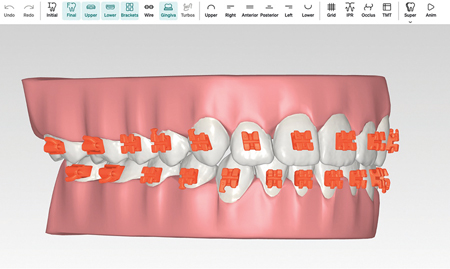

Printed metal appliances,” “sintered metal appliances,” “absolute magic” … however you prefer to refer to the newest form of appliance delivery, its technology is gaining traction in the orthodontic world. Unlike traditional circumferential bands, however, printed appliances have more in common with buccal tubes or large acrylic appliances when it comes to the bonding process. … Read more